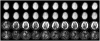

The correction of motion artifacts continues to be a significant problem in MRI. In the case of uncooperative patients, such as children, or patients who are unable to remain stationary, the accurate determination and correction of motion artifacts becomes a very important prerequisite for achieving good image quality. The application of conventional motion-correction strategies often produces inconsistencies in k-space data. As a result, significant residual artifacts can persist. In this work a formalism is introduced for parallel imaging in the presence of motion. The proposed method can improve overall image quality because it diminishes k-space inconsistencies by exploiting the complementary image encoding capacity of individual receiver coils. Specifically, an augmented version of an iterative SENSE reconstruction is used as a means of synthesizing the missing data in k-space. Motion is determined from low-resolution navigator images that are coregistered by an automatic registration routine. Navigator data can be derived from self-navigating k-space trajectories or in combination with other navigation schemes that estimate patient motion. This correction method is demonstrated by interleaved spiral images collected from volunteers. Conventional spiral scans and scans corrected with proposed techniques are shown, and the results illustrate the capacity of this new correction approach.